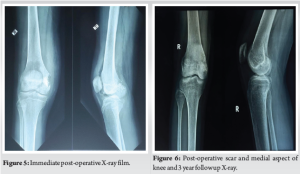

Histopathological analysis of the curetted material revealed viable bone with osteoblastic rimming and nests of chondrocytes, consistent with chondroblastoma. The tumor cells were round to oval with abundant eosinophilic cytoplasm, vesicular nuclei exhibiting nuclear grooves, and occasional multinucleated giant cells. Although classical histological features confirmed the diagnosis, immunohistochemical markers such as S100 and DOG1 were not performed. Postoperatively, the patient was maintained on a knee brace for 4 weeks. She was mobilized without allowing weight bearing on the operated side. Gentle knee bending was started after 4 weeks. Partial weight bearing was allowed after 8 weeks (Fig. 5). Follow-up radiographs showed gradual consolidation of the bone graft and bone substitutes without any recurrence of the tumor. Radiological follow-up was performed using serial X-rays. However, MRI could have offered more detailed evaluation of graft integration, articular cartilage status, and early recurrence, particularly in an epiphyseal tumor. She was allowed full weight bearing after 4 months. Gradually, her knee movements recovered, and she had a full range of motion of the knee without any functional disability. (The rehabilitation protocol was individualized and not based on standardized guidelines). She was followed up clinically and with radiographs for 3 years (Fig. 6). Although the patient was followed for 3 years without recurrence, longer-term surveillance beyond 5 years is ideal given the potential for delayed recurrence in chondroblastoma.